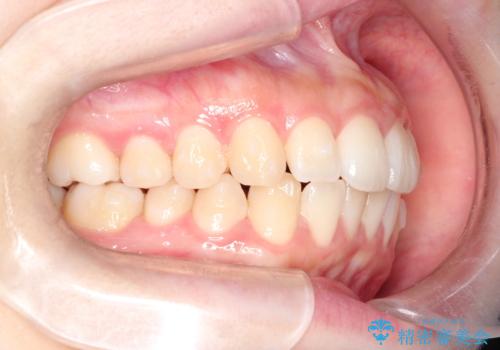

前歯のがたつきをインビザラインで目立たない矯正

- 上下の前歯のがたつきを主訴に来院されました。

マウスピースでの矯正を希望されたので、インビザラインで矯正治療を行うこととしました。

インビザラインではシュミレーションによりどのように歯が動くかを確認して矯正することができるので、患者様も安心して矯正をすることができました。